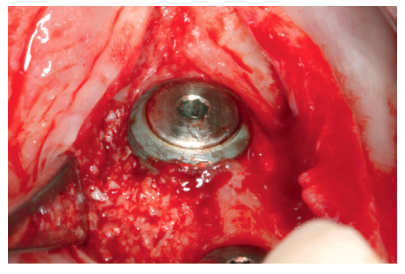

Anitua E, Begoña L, Orive G. Controlled ridge expansion using a two-stage splitcrest technique with ultrasonic bone surgery. Implant Dent 2012; 21: 163-70.

Anitua E, Begoña L, Orive G. Two-stage split-crest technique with ultrasonic bone surgery for controlled ridge expansion: a novel modified technique. Oral Surg Oral Med Oral Pathol Oral Radiol Endod 2011; 112: 708-10.